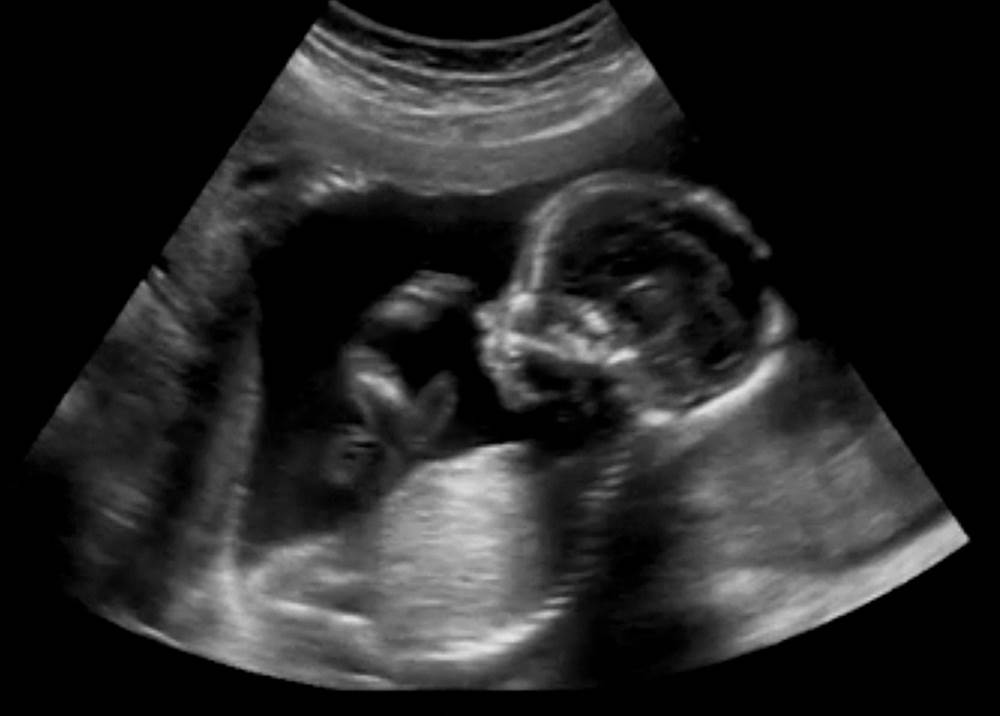

Do 5. tjedna trudnoće srčana cijev počinje spontano kucati, iako je još ne čujete. Ako odete na ultrazvučni pregled u prvom tromjesečju (negdje između 6. i 9. tjedna trudnoće), liječnik će vas pregledati kako bi provjerio kuca li bebi srce. Možda ćete prvi put moći čuti otkucaje srca oko 10. tjedna trudnoće, no to može varirati od trudnice do trudnice.

Ako se još ne čuju otkucaji, ne radite odmah paniku jer je velika vjerojatnost da se vaš sramežljivi fetus krije u kutu maternice ili je u 'nezgodnom' položaju pa vaginalna sonda ne može detektirati svoju metu. Na sljedećem će pregledu liječnik provjeriti je li sve u redu pa su velike šanse da ćete tada moći čuti otkucaje srca svoje bebe.

Do 17. tjedana, mozak fetusa počeo je regulirati otkucaje srca u pripremi za život u vanjskom svijetu. Do ovog je trenutka otkucaji srca bili su spontani. Tijekom ultrazvuka u drugom tromjesečju liječnik će provjeriti strukturu bebina srca i provjeriti postoji li kakva urođena greška.